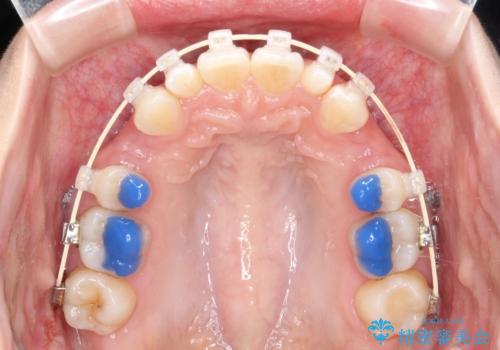

- 矯正装置

- 審美装置

出っ歯をなおすために上顎の前から4番目の歯を抜歯して、引っ込めるのと、前から2番目の歯に通常の大きさのオールセラミックを装着して整った歯並びにすることにしました。

歯の大きさが通常と異なる場合は矯正治療で歯並びだけきれいにしても、整わないことがあります。

その場合はセラミックのかぶせ物を装着して歯の形を正常にすることで、さらに整った歯並びにすることができます。